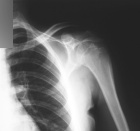

M.S. - 18 year old male with left shoulder pain

Zoom image: Radiological image Radiological image.